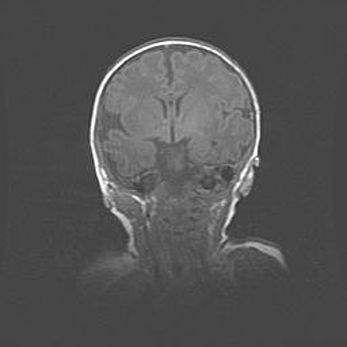

Наружная гидроцефалия с возможной атрофией височных областей.

Возраст: 28 дней

Вес: 3670 г

Пол: мужской

Окружность головы: 38 см

Срок гестации: 40 недель

Гидроцефалия головного мозга у новорожденных – это заболевание, которое характеризуется скоплением избыточного количества спинномозговой жидкости в желудочковой системе головного мозга в результате затруднения её перемещения от места выработки к месту поглощения в кровеносную систему или вследствие нарушения абсорбции. При открытой наружной форме гидроцефалии у новорожденных расширяются и переполняются субарахноидные пространства.

При нормотензивных  формах,  которые,  как  правило,  являются  следствием  перенесенных ишемических  повреждений  паренхимы  мозга,  возможно  сочетание микроцефалии  с нормотензивной гидроцефалией. В основе данных изменений лежит атрофия больших полушарий с преимущественной  локализацией  в  лобно-височных  областях.